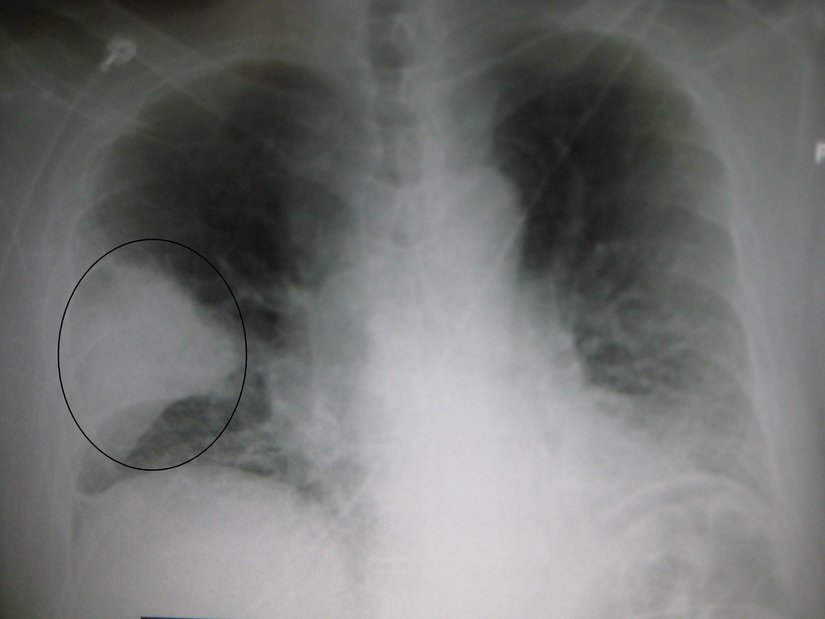

Buna bağlı olarak ateş çıkar, soğuk titremeler yaşanır ve bakteriyel zatürrede yaygın olarak görülen bitkinlik oluşur. Bakteriler, nötrofiller ve civardaki kan damarlarından sızan sıvılar, zatürreye ait tipik göğüs X-ışını taraması fotoğraflarındaki bulutlu görünüme neden olur:

İlk muayeneden sonra hekimin şüphe etmesi halinde göğüs X-rayi, kan testi ve sputum örneği test edilerek teşhis kesinleştirilir. Gerekli görülmesi halinde nabız oksimetrisi ile kandaki oksijen seviyeleri de kontrol edilir. Çocuklarda, yukarıda sözünü ettiğimiz nefes sıklaşmasına dikkat edilmelidir. Stetoskop yoluyla yapılan dinlemelerde hırıltılar duyulabilir.

Tedavi edilmesi halinde birçok zatürre tipi 3-6 gün içinde kontrol altına alınabilmektedir. Tüm semptomların ortadan kalkması ise birkaç hafta sürebilir. Çoğu zaman X-ışını görüntülerindeki bulgular 4 haftada yok olur ve hastalığın öldürücülük oranları oldukça düşüktür (%1 civarındadır). Yaşlı ve savunma sistemi zayıf kişilerde tam iyileşme 12 haftayı bulabilir.